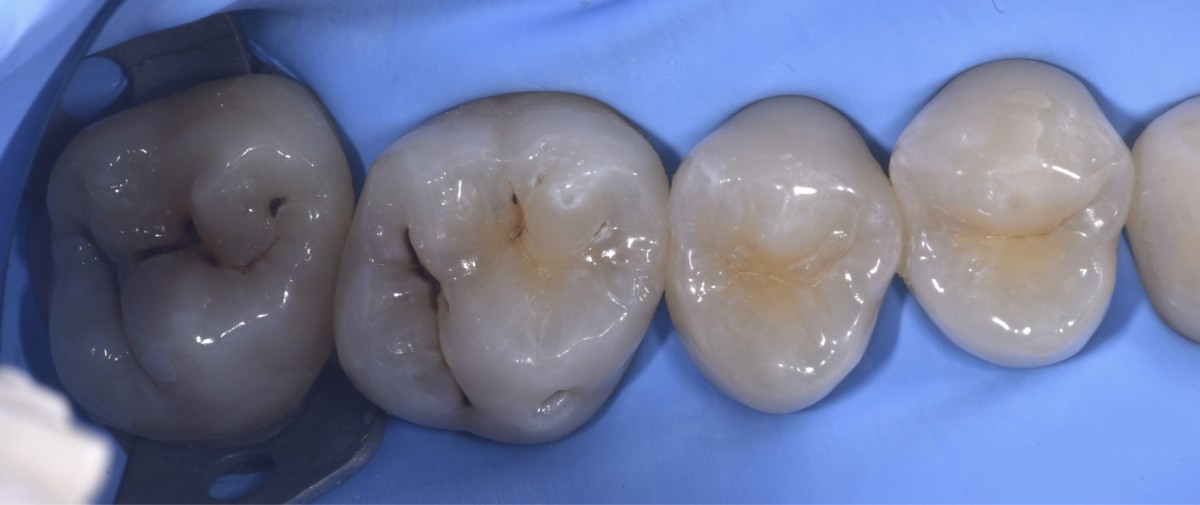

Isolation with rubber dam (Fig.2).

Cavity cleaning of all elements (Fig.3). I started with the cleaning of 2.6, in order to perform a direct inspection of 2.5 distal area. Since 2.5 distal presented a minor decay, without the involvement of the distal marginal crest, a slot approach was followed.